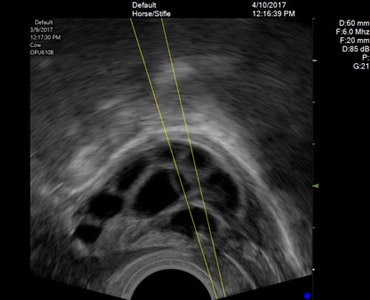

USG Guided Cyst Aspiration

An ultrasound-guided cyst aspiration is a minimally invasive procedure in which ultrasound is used to locate a cyst and guide a thin needle into the cyst to remove the fluid. It is used for the simple (non-cancerous) cyst, filled with clear fluid. It is usually done under IV sedation / G.A. via vaginal route.